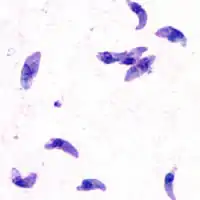

| T. gondii tachyzoites | |

Acute

Acute toxoplasmosis is often asymptomatic in healthy adults.[13][14] However, symptoms may manifest and are often influenza-like: swollen lymph nodes, headaches, fever, and fatigue,[15] or muscle aches and pains that last for a month or more. It is rare for a human with a fully functioning immune system to develop severe symptoms following infection. People with weakened immune systems are likely to experience headache, confusion, poor coordination, seizures, lung problems that may resemble tuberculosis or Pneumocystis jirovecii pneumonia (a common opportunistic infection that occurs in people with AIDS), or chorioretinitis caused by severe inflammation of the retina (ocular toxoplasmosis).[15] Young children and immunocompromised people, such as those with HIV/AIDS, those taking certain types of chemotherapy, or those who have recently received an organ transplant, may develop severe toxoplasmosis. This can cause damage to the brain (encephalitis) or the eyes (necrotizing retinochoroiditis).[16] Infants infected via placental transmission may be born with either of these problems, or with nasal malformations, although these complications are rare in newborns. The toxoplasmic trophozoites causing acute toxoplasmosis are referred to as tachyzoites, and are typically found in various tissues and body fluids, but rarely in blood or cerebrospinal fluid.[17]

While rare, skin lesions may occur in the acquired form of the disease, including roseola and erythema multiforme-like eruptions, prurigo-like nodules, urticaria, and maculopapular lesions. Newborns may have punctate macules, ecchymoses, or "blueberry muffin" lesions. Diagnosis of cutaneous toxoplasmosis is based on the tachyzoite form of T. gondii being found in the epidermis.[30] It is found in all levels of the epidermis, is about 6 by 2 μm and bow-shaped, with the nucleus being one-third of its size. It can be identified by electron microscopy or by Giemsa staining tissue where the cytoplasm shows blue, the nucleus red.[31]

In its lifecycle, T. gondii adopts several forms.[32] Tachyzoites are responsible for acute infection; they divide rapidly and spread through the tissues of the body. Tachyzoites are also known as "tachyzoic merozoites", a descriptive term that conveys more precisely the parasitological nature of this stage.[33] After proliferating, tachyzoites convert into bradyzoites, which are inside latent intracellular tissue cysts that form mainly in the muscles and brain. The formation of cysts is in part triggered by the pressure of the host immune system.[34] The bradyzoites (also called "bradyzoic merozoites") are not responsive to antibiotics. Bradyzoites, once formed, can remain in the tissues for the lifespan of the host. In a healthy host, if some bradyzoites convert back into active tachyzoites, the immune system will quickly destroy them. However, in immunocompromised individuals, or in fetuses, which lack a developed immune system, the tachyzoites can run rampant and cause significant neurological damage.[32]